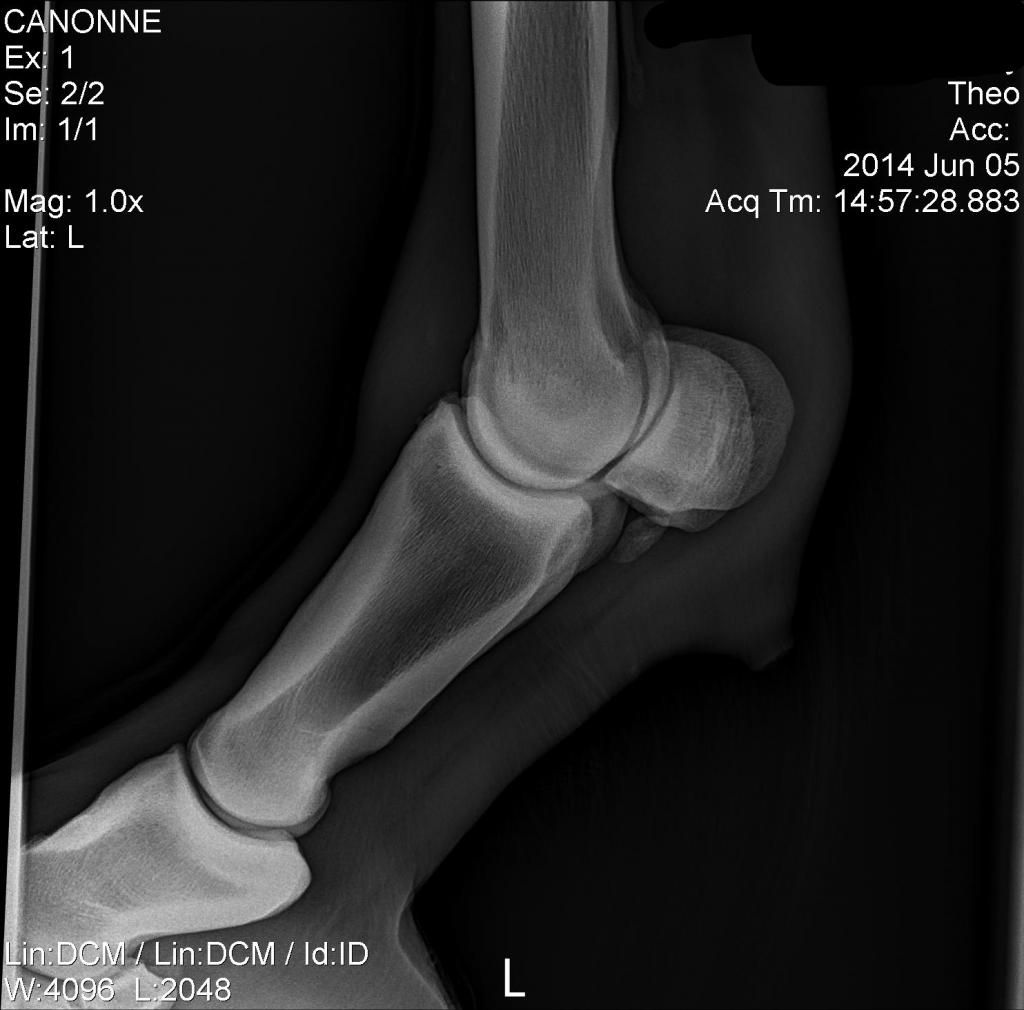

From www.equisearch.com

Radiographs Know What They Can and Can't Tell You Expert advice on Horse Bone Spur Fetlock this condition involves a tear or strain of the suspensory ligament where it branches onto the bones at the back of the. One key indicator of a horse fetlock injury is the appearance of lameness, which can manifest as an unusual. palmar osteochondral disease of the fetlock affects the subchondral bone of the palmar/plantar aspects of the distal.. Horse Bone Spur Fetlock.